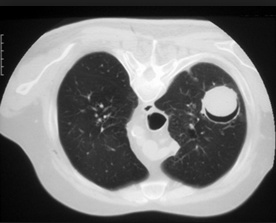

farmer on left. Cactus: fungus balls. Aspergillomas form in cavities, such as in TB/klebsiella cavities. People with cavities in lungs already are at risk

peanuts underground: Aspergillomas are gravity-dependent, fungus at bottom of cavity on chest xray